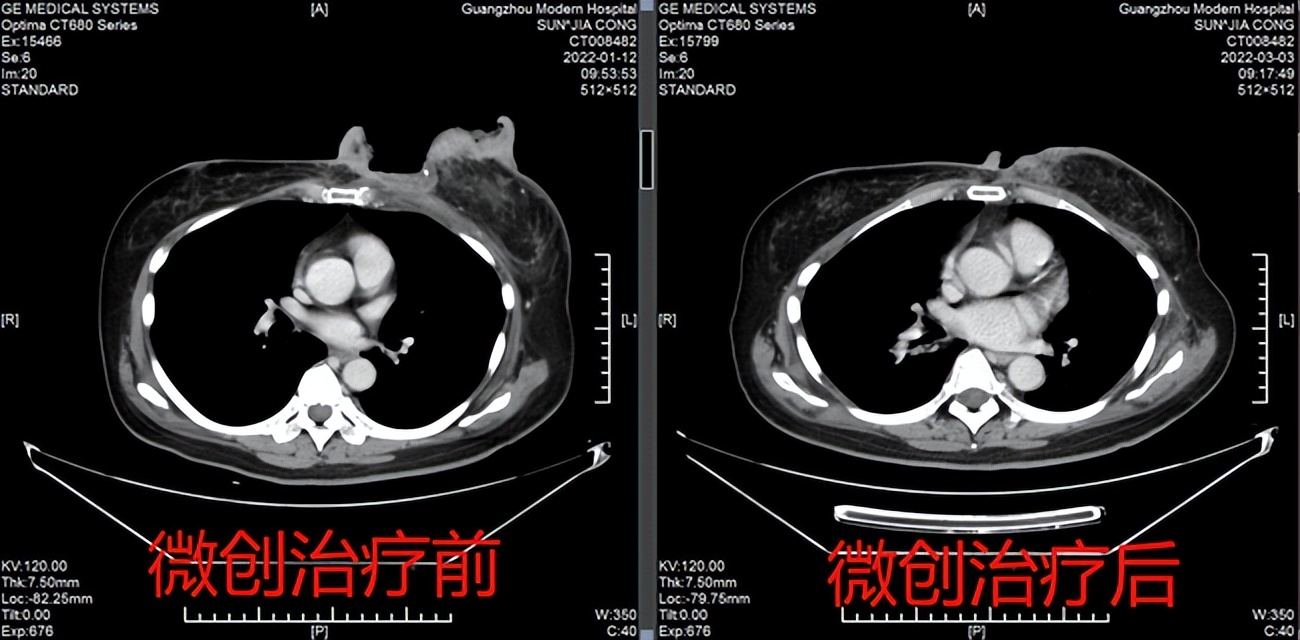

治疗前后CT对比图

据孙女士的管床江医生介绍,孙女士是在1月11日入院的,当时左乳房肿瘤整体呈现菜花样,破溃面大概12*10CM,入院完善检查后考虑为左乳腺癌保乳术后复发并左肾上腺、骨、多发淋巴结转移,IV期。考虑到患者属于乳腺癌晚期,韦主任授团队认为孙女士目前的情况,传统的手术和放化疗并不是最佳的选择。所以给她拟定了微波消融术联合介入动脉灌注化疗和介入栓塞方案。在治疗前,患者的癌胚抗原高达10.38(1月12日测)。在进行首次微波消融术后,患者乳腺肿物明显缩小,在2月7日复查癌胚抗原已降至5.87。整体疗效良好。在整个疗程中给患者做了2次微波消融,并采用双靶治疗联合介入动脉灌注化疗+介入栓塞治疗,3月3日复查CT,患者复发的肿瘤和病变范围较前已明显缩小,复查癌胚抗原为3.23降至正常范围。体表的肿瘤坏死脱落,基本愈合。